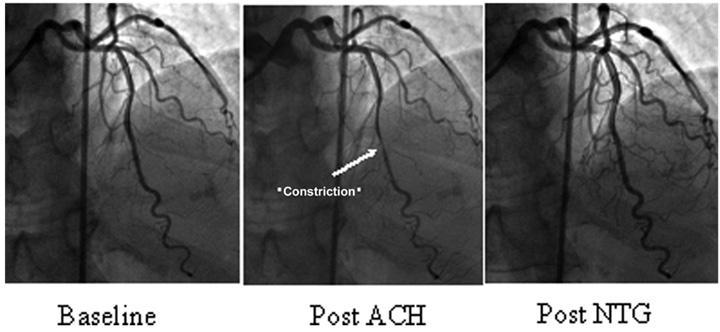

A síndrome X cardíaca constitui uma entidade clínica semelhante a angina do peito, onde há isquemia miocárdica, porém com coronárias…